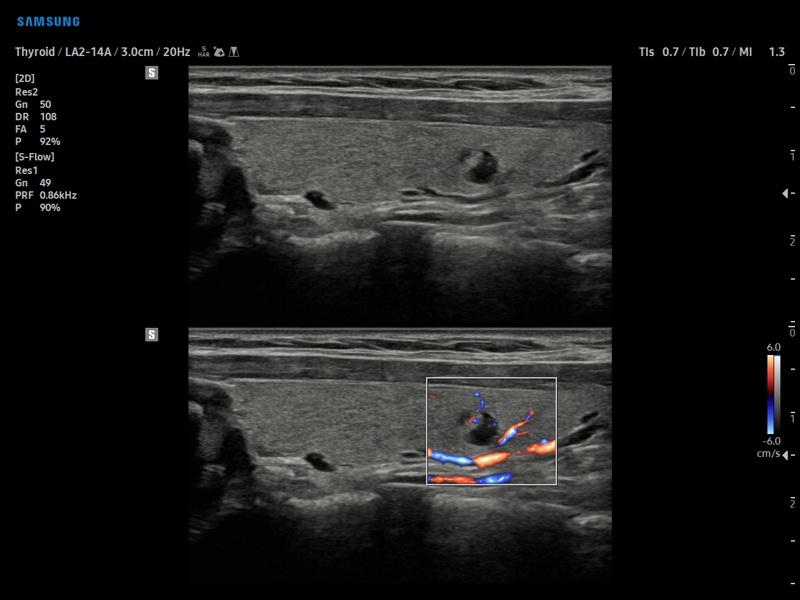

• МодульS-Detect Thyroid- программа автоматического обнаружения образований и анализа щитовидной железы, измерение и классификация по системе системе TI-RADS.

• Модуль S-Detect Thyroid - программа автоматического обнаружения образований и анализа щитовидной железы, измерение и классификация по системе системе TI-RADS.